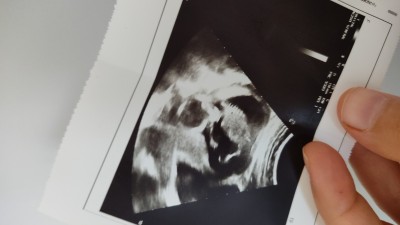

Kızlar 15 haftalık cinsiyeti ne gibi duruyor

Hiç birşey belli olmuyor ki

Anam bebe nerde :-)

Ben kıza benzettim